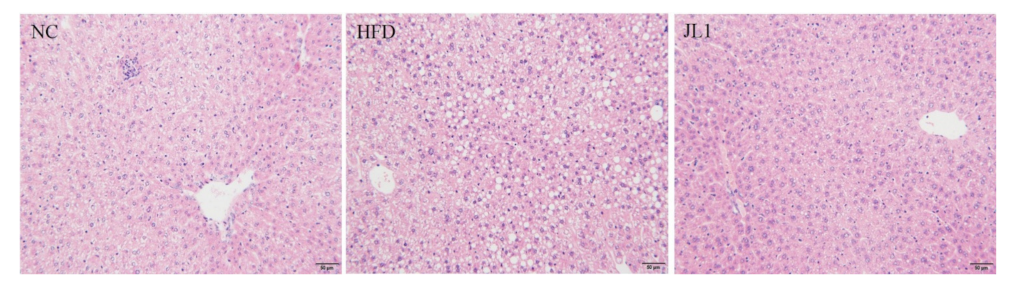

3.5. Liver Histological Image of Mice